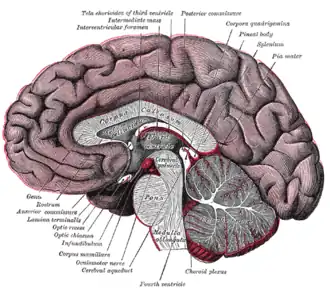

Sagittal section of a brain, front part to the left. The corpus callosum can be seen in the center, in light gray | |

The corpus callosum (Latin for "tough body"), also callosal commissure, is a wide, thick nerve tract, consisting of a flat bundle of commissural fibers, beneath the cerebral cortex in the brain. The corpus callosum is only found in placental mammals.[1] It spans part of the longitudinal fissure, connecting the left and right cerebral hemispheres, enabling communication between them. It is the largest white matter structure in the human brain, about 10 cm (3.9 in) in length and consisting of 200–300 million axonal projections.[2][3]

The corpus callosum forms the floor of the longitudinal fissure that separates the two cerebral hemispheres. Part of the corpus callosum forms the roof of the lateral ventricles.[5]

The corpus callosum has four main parts – individual nerve tracts that connect different parts of the hemispheres. These are the rostrum, the genu, the trunk or body, and the splenium.[4] Fibres from the trunk and the splenium, known together as the tapetum ("carpet"), form the roof of each lateral ventricle.[6]

The front part of the corpus callosum, towards the frontal lobes, is called the genu ("knee"). The genu curves downward and backward in front of the septum pellucidum, diminishing greatly in thickness. The lower, much thinner part is the rostrum and is connected below with the lamina terminalis, which stretches from the interventricular foramina to the recess at the base of the optic stalk. The rostrum is named for its resemblance to a bird's beak.

The end part of the corpus callosum, towards the cerebellum, is called the splenium. This is the thickest part, and overlaps the tela choroidea of the third ventricle and the midbrain, and ends in a thick, convex, free border. Splenium translates as "bandage" in Greek.

The trunk of the corpus callosum lies between the splenium and the genu.

The callosal sulcus is a sulcus that separates the corpus callosum from the cingulate gyrus.

On either side of the corpus callosum, the fibers radiate in the white matter and pass to the various parts of the cerebral cortex; those curving forward from the genu into the frontal lobes constitute the forceps minor (also forceps anterior) and those curving backward from the splenium into the occipital lobes, the forceps major (also forceps posterior).[4] Between these two parts is the main body of the fibers, which constitute the tapetum and extend laterally on either side into the temporal lobe, and cover in the central part of the lateral ventricle. The tapetum and anterior commissure share the function of connecting left and right temporal lobes.

The anterior cerebral arteries are in contact with the undersurface of the rostrum; they arch over the front of the genu and are carried along the trunk, supplying the front four-fifths of the corpus callosum.[7]